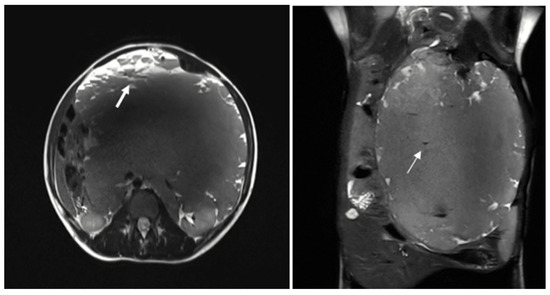

The patient was subsequently admitted for further evaluation, and an abdominal MRI was performed. Imaging sequences included T2-weighted sequences and T1-weighted sequences, with and without fat suppression. However, due to limited patient compliance, the study was interrupted before the contrast agent administration. Despite these limitations, MRI confirmed the presence of a large multiloculated mass with peripheral cystic components exhibiting fluid-debris levels (Figure 2).

Figure 2. The multiloculated mass shows variable signal intensity on T2 sequences and presents cystic formations peripherally, exhibiting fluid-debris levels (thick arrow). Some calcified spots with low T2WI signals were also noted within the mass (thin arrow).